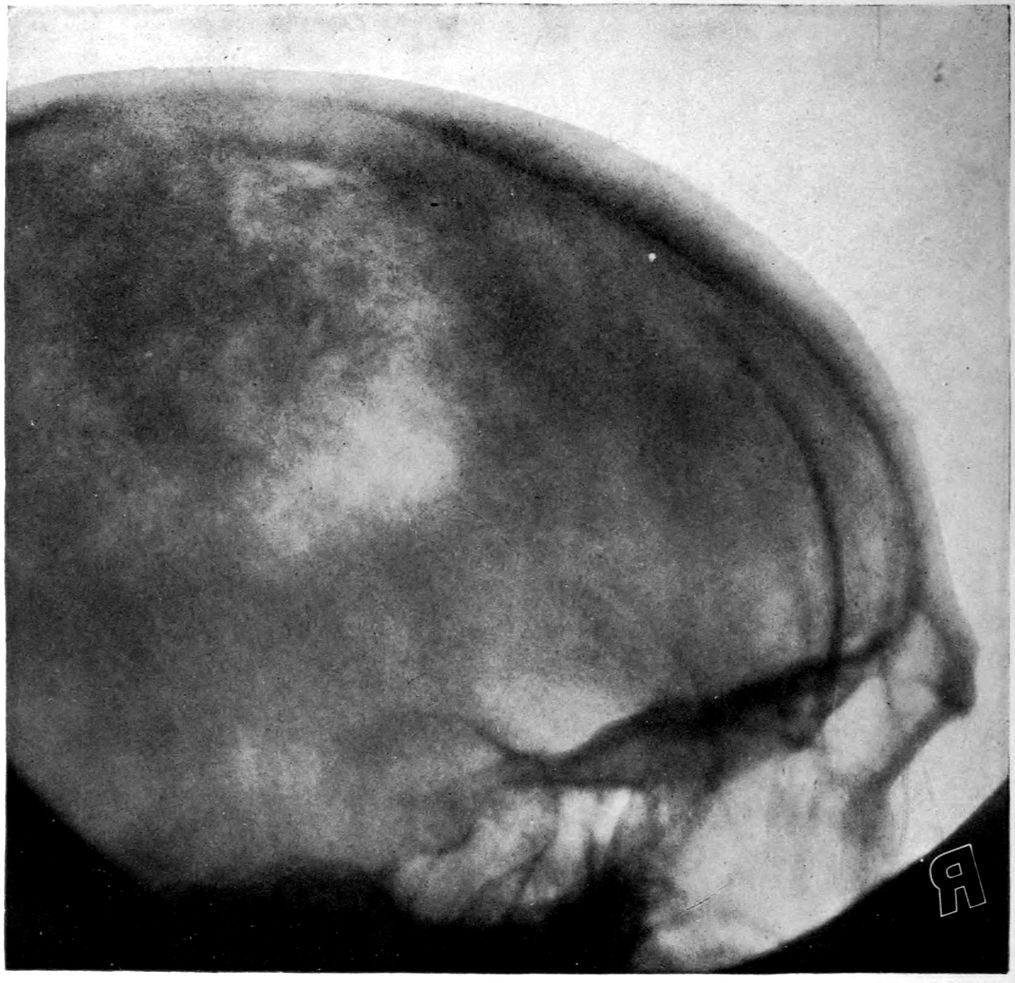

The autopsy findings were as follows:

Head: Calvarium of moderate thickness; diploë present; dura slightly adherent over bregmatic region. Longitudinal sinus contains cruor clot. Dura is somewhat thickened and slightly more opaque than normal. Pacchionian granulations, small but fairly numerous. Pia contains throughout a considerable excess of clear 44serous fluid. The convolutions in general are of good breadth and proportion. There is an atrophic area roughly circular in outline and about 2 cm. in diameter in the posterior part of the right third frontal convolution corresponding to Broca’s area on the opposite hemisphere. The space thus formed is filled with edema held by the pia. On the left side is a similar subpial collection which covers the site of the posterior portions of all of the third frontal convolutions, parts of the lower end of the precentral convolution, and the whole of the first temporal convolution, which have disappeared entirely. The basal vessels show slight changes.

Cerebellum and basal ganglia are grossly normal.

Vascular neurosyphilis—effects of syphilitic thrombosis of Sylvian artery 10 years before death. (Case 4.)